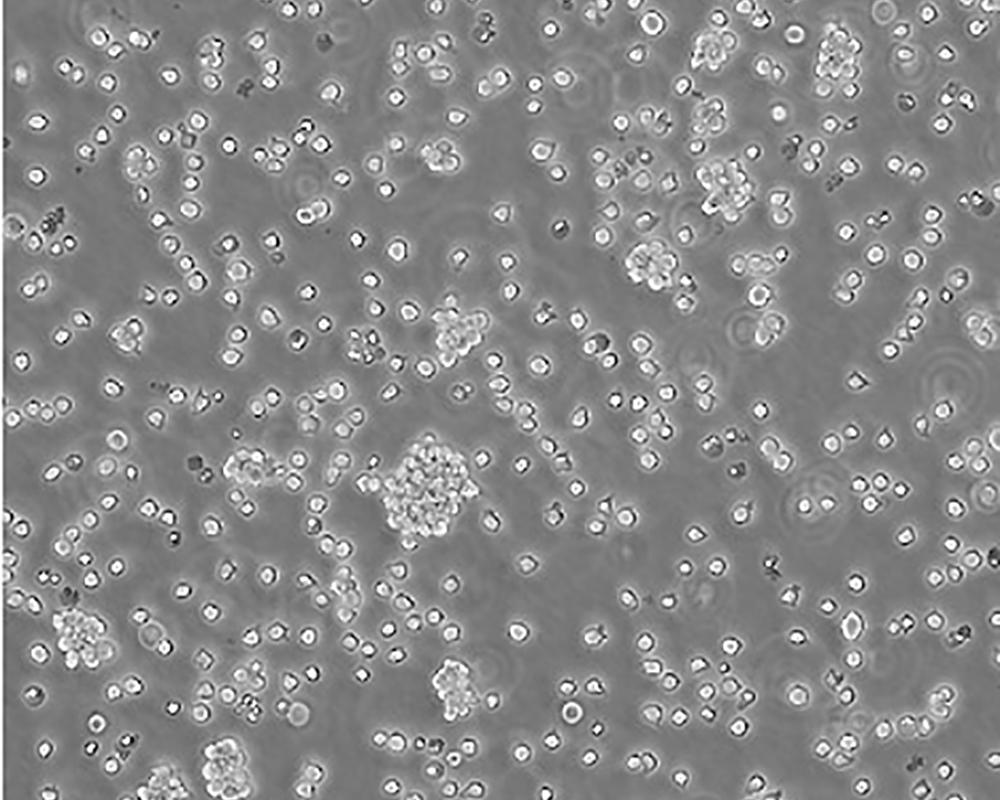

Jurkat, Clone E6-1 [Jurkat E6-1]

人T淋巴細胞白血病細胞

急性T淋巴細胞白血病;男性

suspension

lymphoblast

該細胞是Jurkat-FHCRC細胞株(Jurkat細胞株的衍生)的一個克隆。Jurkat細胞株來源于一個14歲男孩的外周血。經(jīng)佛波酯和外源凝集素或抗T3單克隆抗體誘導后可產生大量IL-2(IL-2的產生需兩種類型的誘導劑);表達T細胞受體、CD3